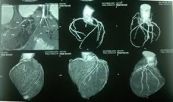

Chụp động mạch là sử dụng thuốc nhuộm và máy ảnh đặc biệt (soi huỳnh quang) để chụp lưu lượng máu trong động mạch (như động mạch chủ) hoặc tĩnh mạch (như tĩnh mạch chủ). Chụp động mạch có thể được sử dụng để nhìn vào các động mạch hoặc tĩnh mạch ở đầu, cánh tay, chân, ngực, lưng hoặc bụng. Bài viết dưới đây sẽ nói rõ hơn về phương pháp xét nghiệm này, mời các bạn tham khảo!